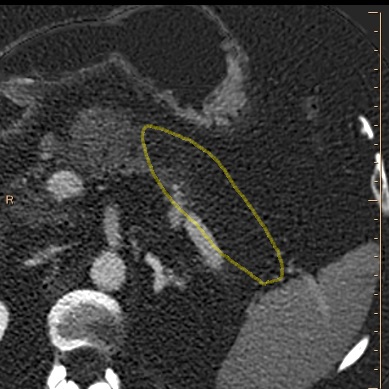

Iodine map shows absent perfusion (outlined in yellow), consistent with necrosis in body and tail